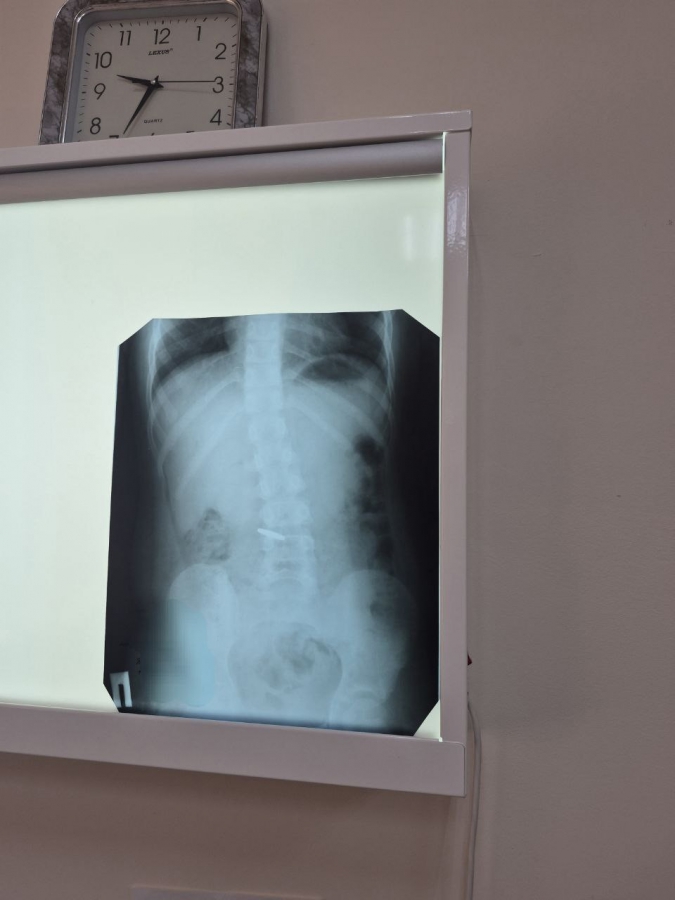

Медики поделились, что в минувшую субботу выдался «жаркий» день: из сорока обратившихся практически каждый пятый пациент – ребенок. Например, в медицинское учреждение 13 сентября поступил младенец в возрасте 1 года 10 месяцев с химическим ожогом пищевода: ребенок выпил уксус. В настоящее время малыш находится в реанимации, состояние его оценивается как стабильно тяжелое. Ребенка переведут в Саратов, поскольку в Балакове не предусмотрен аппарат для проведения ФГДС такому маленькому пациенту.

Два пациента обратились с проглатыванием инородных тел – оба проглотили монеты. В одном случае предмет вышел естественным путем, во втором потребовалась операция – извлечена монета номиналом 10 рублей.